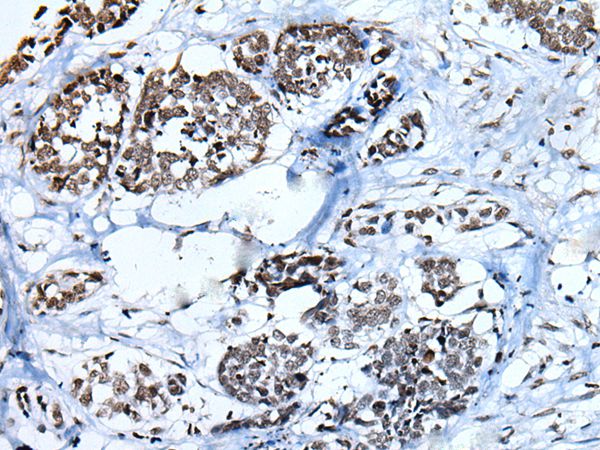

Immunohistochemical analysis of paraffin-embedded Human esophagus cancer tissue using Histone H3 Antibody.